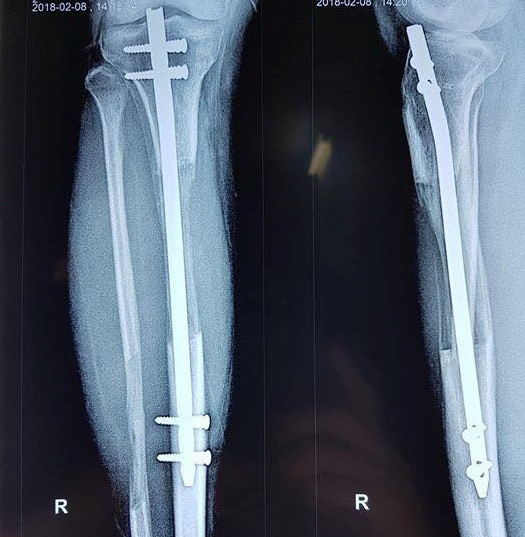

Hundreds of leg lengthening surgeries have been carried out in the Military 108 Hospital's Department of General Trauma and Orthopedics in Hanoi, the unique infirmary in Vietnam can perform such operation.

Surgeons said patients will undergo three operations. The bone to be lengthened is cut. Metal pins or screws are placed through the skin and into the bone. Pins are placed above and below the cut in the bone. Stitches are used to close the wound.

A metal device is attached to the pins in the bone. It will be used later to very slowly (over months) pull the cut bone apart. This creates a space between the ends of the cut bone that will fill in with new bone.

From 2011, the hospital surgeons has just placed four screws. It takes two or three months to recover.